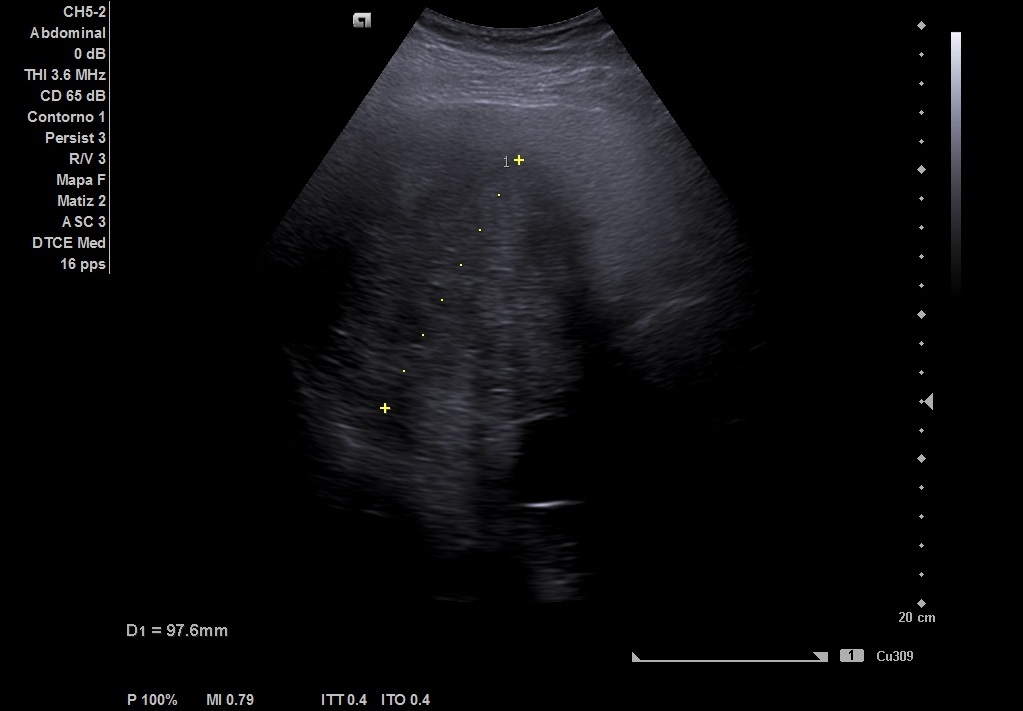

Visualizamos hígado con lesión en cuadrante hepático derecho, segmentos 5, 6 y 7, de 8 x 8 cm. No capta Doppler. Vesícula biliar, vena porta, páncreas y bazo normales. Riñones de tamaño y ecoestructura sin hallazgos patológicos, descartándose alteraciones de la vía excretora.

El paciente comenta hermano intervenido a nivel cardiaco en la infancia, posiblemente de un quiste hidatídico.